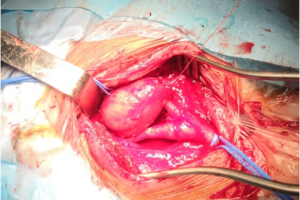

В мае 2019 года хирургами центра сосудистой хирургии им. Т. Топпера была выполнена уникальная операция по удалению гигантского образования шеи, которое давило на сосуды и нервы, угрожая жизни пациента. При исследовании структуры опухоли под микроскопом было установлено, что это шваннома (невринома) – вид доброкачественной опухоли, произрастающей из клеток миелиновой оболочки нерва. Послеоперационный период протекал гладко и на 7 сутки в удовлетворительном состоянии пациент был выписан.